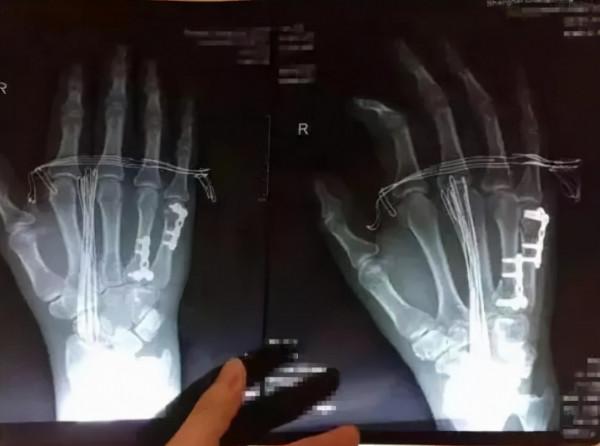

這種方法就是將鋼板植入到身體內,目前所採用的鋼板材質分為不鏽鋼,鈦合金以及鈷合金這幾種材質,不易生鏽,不易腐蝕,可以幫助骨骼部位快速癒合,但是鋼板的位置不同,後續的處理方法也不同。

1、如果是在人的手臂腕骨等比較淺地表面板處放入了鋼板,這樣在日常活動的時候會產生不適感,而且還可能會因為反覆摩擦從而出現感染,這種情況下在康復之後就要取出鋼板。